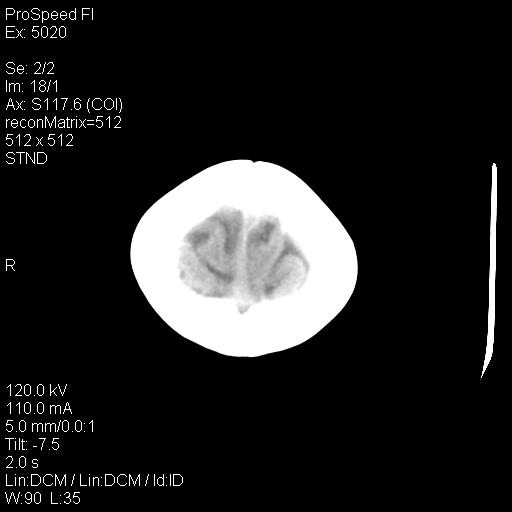

标题: PED1637:M 6Y 顶部无痛性包块两月。 [打印本页]

标题: PED1637:M 6Y 顶部无痛性包块两月。

2、颅骨局部缺失,边缘光滑、整齐

颅骨的病损表现为内外颅骨板层不规则的锋利的破坏,形成“斜边缘”,有一定的特点

颅骨为好发部位,生长缓慢,常位于顶骨、枕骨及颞骨,表现为颅骨缺损,呈圆形或椭圆形,边界清,无硬化

事发冠状缝与矢状缝交界区,密度较低,考虑表皮样囊肿可能性大,其次不除外嗜酸性肉芽肿